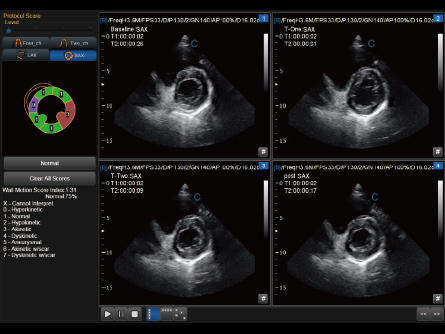

Potencie su práctica en Atención Primaria con las máquinas de ultrasonido de CHISON diseñadas para versatilidad y precisión. Nuestros productos están adaptados para abordar una amplia gama de necesidades de diagnóstico, ofreciendo interfaces fáciles de usar para exámenes eficientes. Las soluciones de ultrasonido de Atención Primaria de CHISON proporcionan imágenes claras y controles intuitivos, respaldando a los médicos generales en la realización de diagnósticos precisos y en la atención integral de los pacientes.